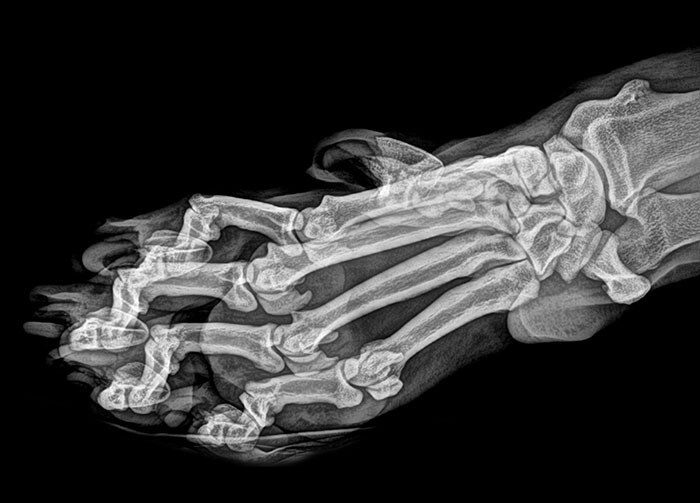

«С нижними зубами мудрости мне не повезло»